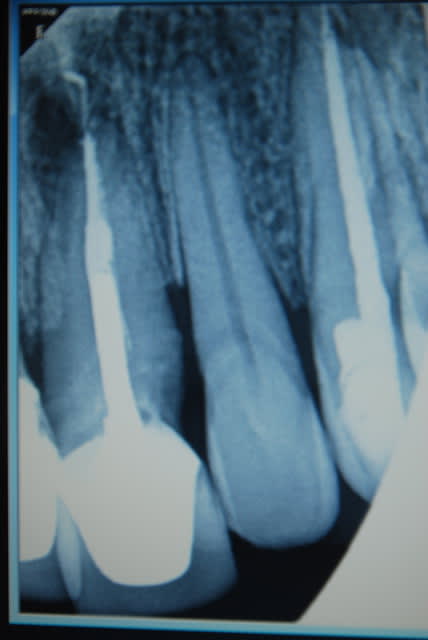

Je viens de revoir le patient et je peux vous apporter quelques précisions ainsi que des photos( désolé si la qualité n'est pas parfaite).

Patient de 45 ans, fumeur, motivé mais ne pouvant se payer d'implants.

Il a déjà vu plusieurs confrères qui lui ont proposé uniquement ( selon ses dires) une solution implantaire pour 12-11-21-22-23. Il souhaite du fixe...

En ce qui concerne la paro, la 12 est en mobilité stade 2, la 22 en stade 1 les autres étant non mobiles. Le sondage de 12 à 22 est de 3 mm, sauf en mésiale de 12 ( 6mm). La gencive est inflammatoire ( logique à la vue de l'inadaptation des couronnes, et des caries radiculaires).

Je pense lui proposer la solution du bridge avec 13,11,21,22, 24,25., même si la 13 est saine... Je prévoyais de reprendre l'endo de 22 mais la taille du tenon et sa longueur m'ont refroidi, peut être qu'une chir endo et obturation à rétro serait plus appropriées... Je prévois bien sur un surfaçage ainsi qu'un assainissement paro, une fois le bridge provisoire en place.

Tu as surtout un gros chantier paro à gérer. Et je ne pense pas que le tenon de la 22 soit si difficile à descendre, accessoirement l'endo de la 11 est aussi à revoir ( et là le tenon semble plus maousse ).